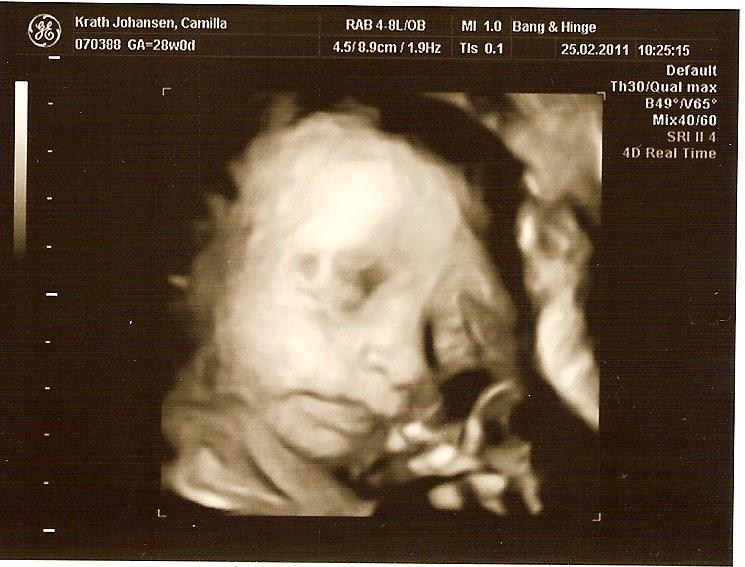

Jeg gjorde det i uge 30, og jeg vil IKKE anbefale at gøre det senere.

Selvom vores søn var lille, så havde han ikke meget plads at ligge på i uge 30, og da de ligger "lidt klemt", så blir det sværere at se noget, jeg større de blir. Vi fik nogen rigtig gode billeder, men det tog en del tid, fordi hans arme lå presset op foran hans ansigt og det er jo svært lige at flytte dem

Men sikke en stor oplevelse